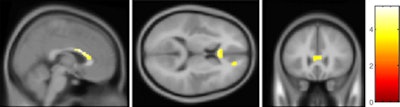

Using a voxel-based analysis, the researchers evaluated the corpus callosum, which connects the right and left hemispheres of the brain and facilitates communication between the two regions, and the right superior frontal gyrus, which coordinates an individual's sensory system and self-awareness.

They found that OCD patients demonstrated significantly increased fractional anisotropy in the corpus callosum and in the white matter of the right superior frontal gyrus, compared with the healthy control subjects.

| Parametric maps superimposed on 3D T1-weighted images show that OCD patients had significantly increased fractional anisotropy in the corpus callosum (above) and right superior frontal gyrus (below). Images courtesy of Radiology. |

The mean fractional anisotropy for the corpus callosum in the OCD group was 0.499 ± 0.038, compared with 0.446 ± 0.039 in the control group. For the white matter of the right superior frontal gyrus, the mean fractional anisotropy in the OCD group was 0.411 ± 0.024, compared with 0.375 ± 0.025 among healthy subjects.

In the increased fractional anisotropy areas, axial diffusivity was greater in OCD patients compared with the control subjects, while radial diffusivity was not significantly different.